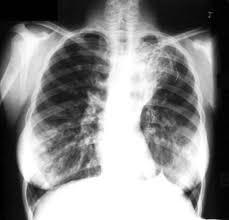

Bronchiectasis is an uncommon disease, most often secondary to an infectious process, that results in the abnormal and permanent distortion of one or more of the conducting bronchi or airways. First described by Laennec in 1819, later detailed by Sir William Osler in the late 1800s, and further defined by Reid in the 1950s, bronchiectasis has undergone significant changes in regard to its prevalence, etiology, presentation, and treatment.Bronchiectasis can be categorized as a chronic obstructive pulmonary disease manifested by airways that are inflamed and easily collapsible, resulting in air flow obstruction with shortness of breath, impaired clearance of secretions